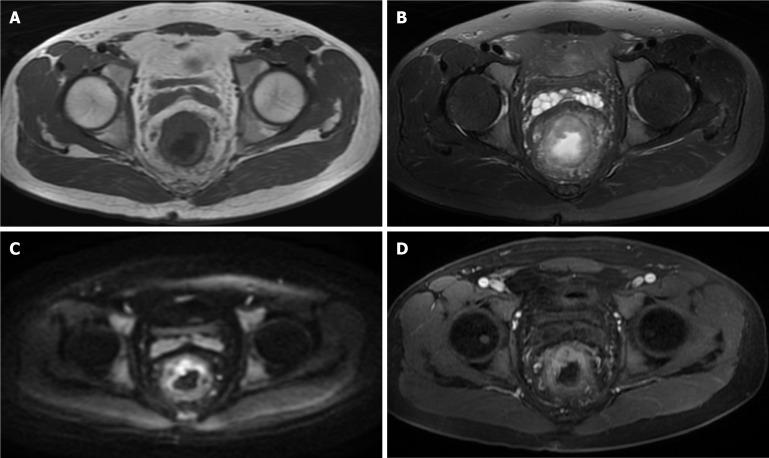

To evaluate the predictive value of dynamic contrast-enhanced-magnetic resonance imaging (DCE-MRI) parameters and serum biomarkers [carbohydrate antigen (CA) 19-9, CA125] for determining T stage and differentiation grade in rectal cancer.

We conducted a retrospective review of clinical data from 126 patients who were pathologically diagnosed with rectal cancer between January 2021 to June 2024. Each patient underwent DCE-MRI scans and serum tests for CA19-9 and CA125. Receiver operating characteristic curves were utilized to assess the diagnostic value of DCE-MRI parameters, including volume transfer constant (Ktrans), rate constant (Kep), and volume fraction of extravascular extracellular space (Ve), as well as serum biomarkers for staging and grading rectal cancer. The DeLong test algorithm was employed to evaluate differences in diagnostic performance among the various indicators.